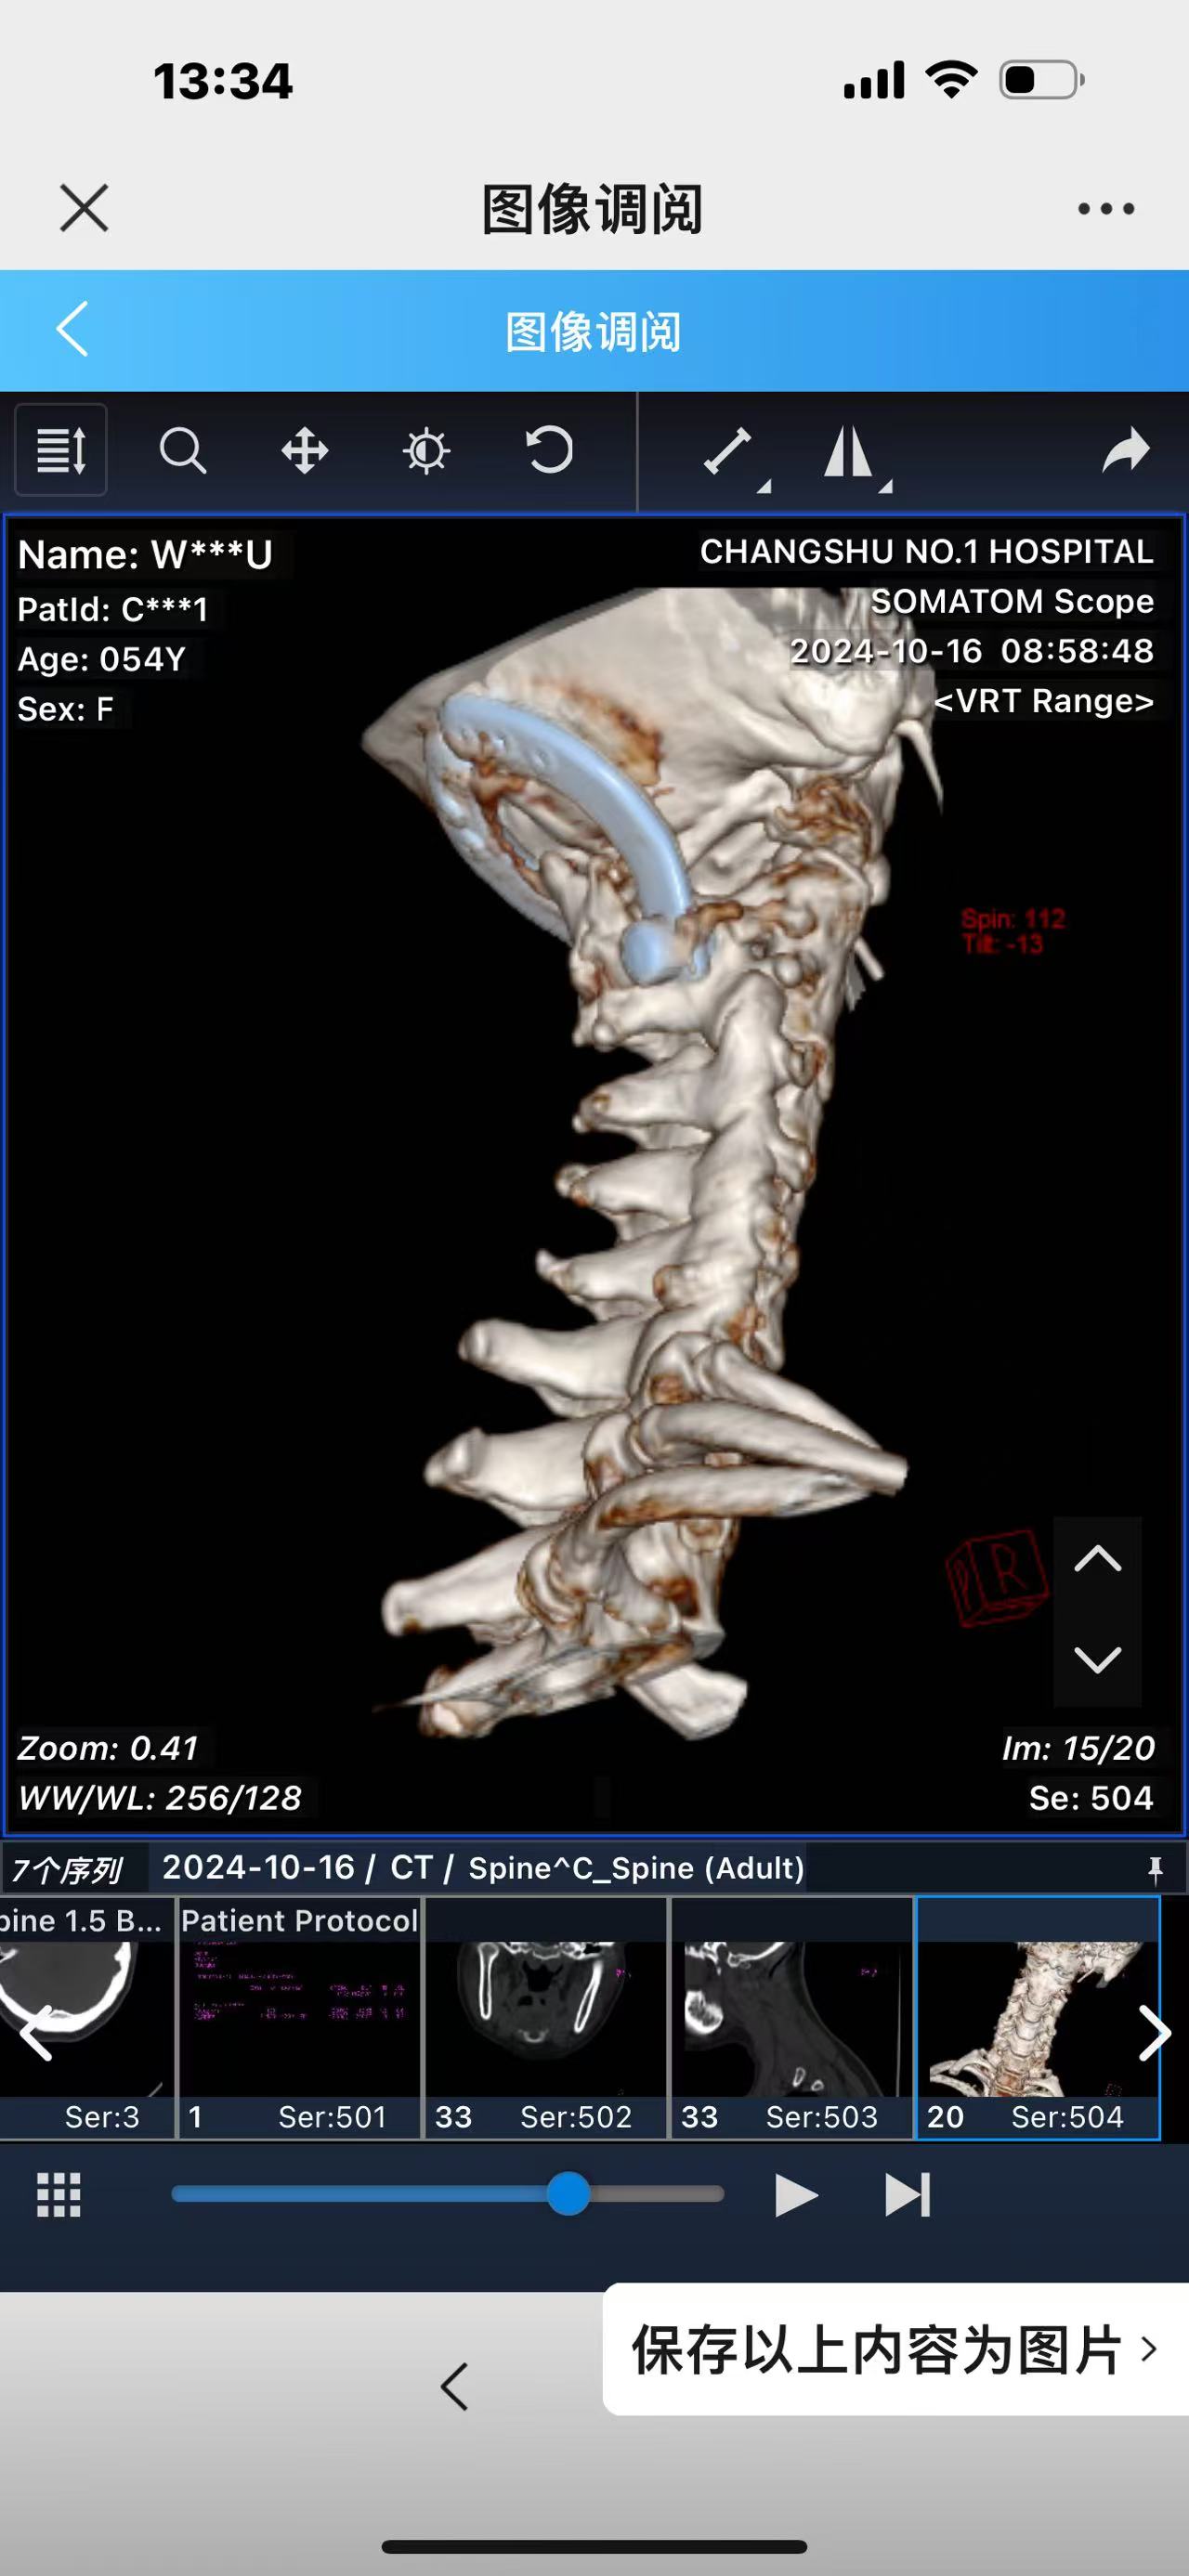

• 诊断:寰枢椎脱位,颅底凹陷

• 术后影像:

• 2024.10.20,复查,对位良好,偶尔会肩甲骨酸,坐下就不酸。